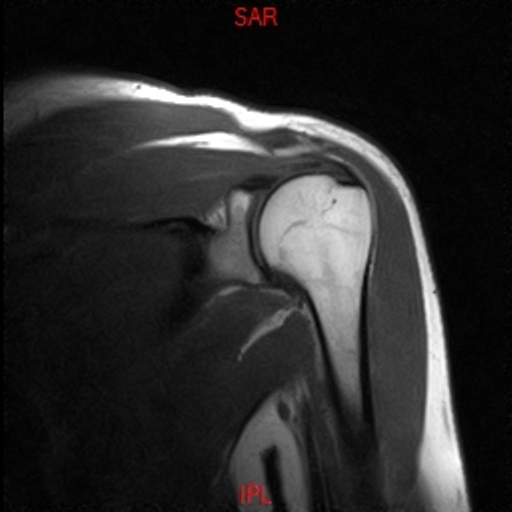

• Resonancia PATOLÓGICA DE HOMBRO - FRACTURA TROQUITER -  COR T1

• Resonancia PATOLÓGICA DE HOMBRO - FRACTURA TROQUITER Y EDEMA OSEO -  COR T2 WF

• Resonancia NORMAL HOMBRO COR T2 WF

• Resonancia NORMAL HOMBRO COR T1